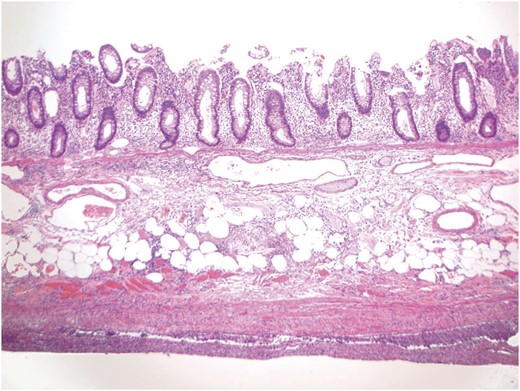

A 52-year-old male with a history of Stage IIIb melanoma initially underwent a wide local excision with a sentinel lymph node biopsy for a 2.1 mm in-depth melanotic lesion of his left upper arm melanoma. The sentinel lymph node biopsy at that time was negative for malignancy. Two years later he returned with an in-transit metastasis proximal to the original lesion. He underwent re-excision and axillary lymph dissection at that time. Following the removal of this lesion he was started on ipilimumab at 6 mg/kg. He had completed two injections spaced 1 month apart before he returning to clinic with complaints of diarrhea and significant abdominal pain. At that time a CT scan (Fig. 1) and colonoscopy with biopsy were performed, both were consistent with active colitis. Adjuvant therapy was suspended and the patient was started on prednisone at standard dosage. The patient’s symptoms improved over the course of the next week. However, 2 weeks following initiation of immunosuppresion he presented acutely to the emergency department with hypotension, peritonitis and free air beneath the diaphragm. He was taken to the operating room for exploratory laparotomy. Following entrance to the abdomen via a midline incision extensive inflammation was noted from the terminal ileum to the mid-transverse colon. Perforation of the cecum was the salient finding (Fig. 2). A right extended hemicolectomy was performed with end ileosotomy. Pathology was consistent with ipilimumab-induced perforation colitis (Fig. 3). The patient tolerated the procedure and was cared for in the surgical intensive care unit overnight before being released to the general surgery floor in the morning. His postoperative course was complicated by continued symptomatic enteritis for the next 2 weeks; however by Week 3 repeat colonoscopy revealed evidence of regeneration and healing of the colonic mucosa. He was discharged home and will likely be scheduled for ileostomy takedown in 6–8 weeks following cessation of immunosuppression.

A representative section showing inflammation involving all layers of the colonic wall. The submucosal layer is slightly edematous, while the muscular layer is attenuated. The prominent acute and chronic inflammation involving the pericolonic soft tissue and peritonealized surface is consistent with the clinical impression of perforation.